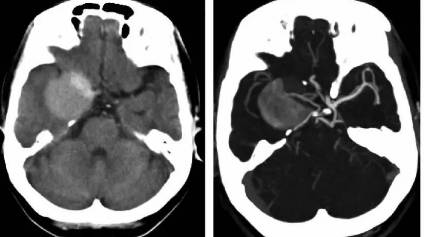

CT:高密度,T1WI,T2WI流空信号

CTA:动脉瘤合并血栓。

①无血栓动脉瘤:平扫为圆形等或略高密度影,边缘清楚,病灶周围无或轻度水肿。增强有均匀强化。

②部分血栓动脉瘤:平扫有血流的部分为等密度,而血栓部分密度稍高。增强扫描,瘤腔部分强化,血栓部分不强化。如果血栓是偏心型,强化部分则显示为半圆形、新月形等。如果血栓位于血管腔内的周边,增强扫描动脉瘤中心的瘤腔和外层囊壁均有强化,形成中心高密度和外围高密度环,中间隔以等密度带,称之“靶形征”。

③完全血栓动脉瘤:平扫为等密度,其内可有点状钙化,瘤壁可见蛋壳样弧形钙化。增强扫描仅有囊壁环状强化,其内血栓无强化。